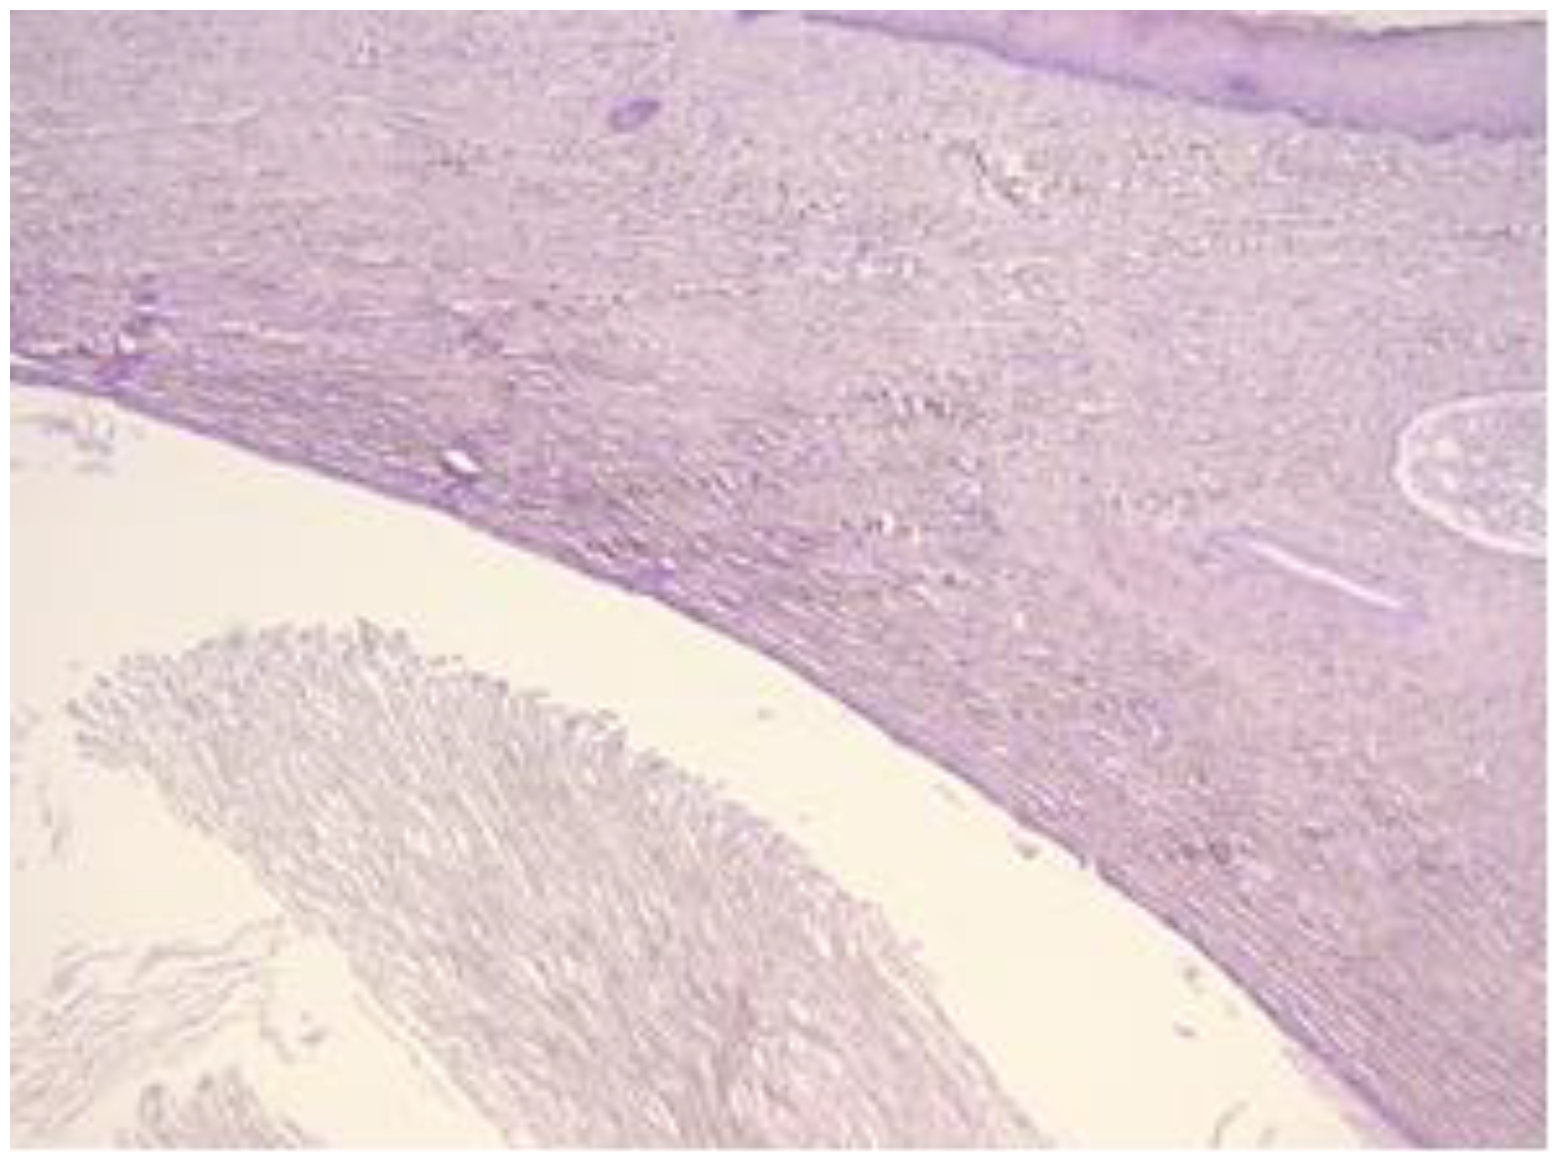

The exo-cervix shows a cystic structure in the deeper layers that is filled with an amorphic, eosinophilic, lamellar substance (Figure 3). The cyst is lined by stratified epithelium resembling squamous epithelium that reminds us of the typical structure found at the level of the endo-exocervical junction (Figure 4).

Figure 4.

Cyst is lined by a stratified epithelium that resembles a squamous epithelium, similar in appearance to the endo-exocervical junctional area (HE staining, 10×).